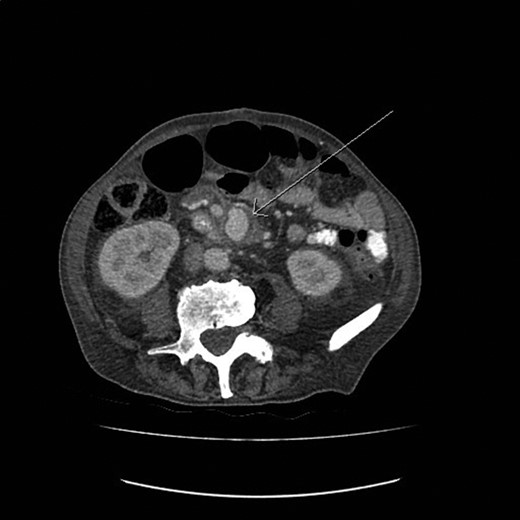

Exploratory laparotomy was performed, and after meticulous dissection, the proximal and distal ends of the SMAA were both isolated and clamped. The entire aneurysm and the surrounding inflammatory tissue, including lymph nodes, were fully excised (Figs 2 and 3). Due to good collateral flow (intestine), no bypass or interposition grafting was deemed necessary. Given the lack of any identifiable primary or secondary sources and normal echocardiogram, blood cultures were obtained and sent (along with the specimen) for histology and microbiology examinations. Subsequent blood culture revealed EF (Day 1) that was also later identified on the specimen. The histology demonstrated focal endothelial necrosis and neutrophil infiltration. The patient was immediately started on antibiotics (vancomycin) according to the sensitivity of the culture for a period of 6 weeks and discharged on the 6th postoperative day. Follow-up CT at 3 months demonstrated complete resection of the aneurysm with no inflammatory changes. The repeated blood culture and serology for inflammatory markers were normal, and the patient reported no complication on follow-up (Fig. 4).

The postoperative CT image (3D reconstruction) demonstrating complete resection of the aneurysm.